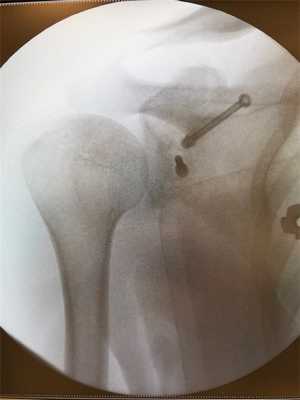

Редкое осложнение после артроскопический операции Латарже - это миграция винта. В данном случае удаление металлоконструкции не требуется, т.к. Пересаженный костный блок прирос и функция полностью восстановилась.